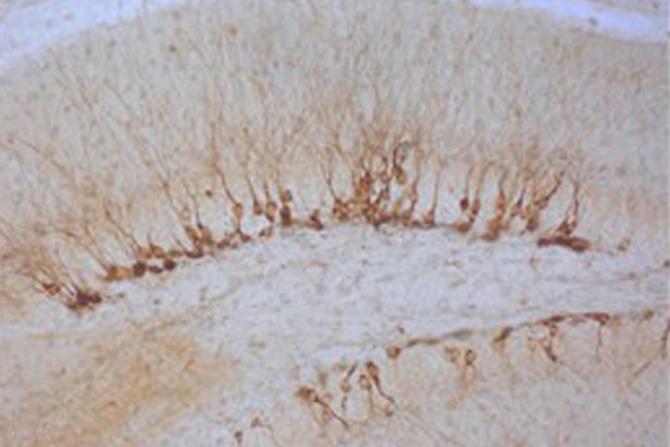

Neuronas inmaduras en el giro dentado de un ratón sobrexpresando los factores de Yamanaka. (Foto Alberto García Rodríguez/CBMSO)